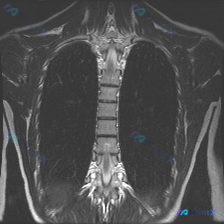

整理了一份影像分析资料,觉得这个矛盾点挺有意思的,拿出来和大家讨论。 资料背景是:一张胸部MRI T2加权像(冠状位),临床核心诉求是排查脊柱侧弯。 先放几个关键的影像所见: - 肺实质、纵隔、胸膜腔、胸壁软组织都未见明显异常信号或占位 - 报告写了“胸椎椎体及附件形态基本完整”、“脊柱旁软组织未见...

整理到一份胸椎MRI冠状位T2加权的影像资料,先把核心阳性发现和阴性排查点列出来,大家看看思路会怎么走。 核心阳性表现: - 胸椎整体存在轻度侧向弯曲,左右不对称 关键阴性排查(目前MRI层面): - 脊髓信号正常,连续性好,无受压、增粗或中央管扩张 - 各椎体形态规则,骨髓信号均匀,未见压缩骨折、...